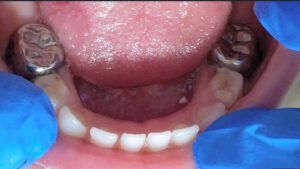

Korony stalowe stosowane są do odbudowy tkanek zębów trzonowych mlecznych. Są uznawane jako jedna z najlepszych form uzupełnień u dzieci.

Wskazaniem do wykonania koron stalowych są przede wszystkim ubytki próchnicowe, które obejmują co najmniej dwie powierzchnie zębów mlecznych, odbudowa zębów pourazowych lub z zaburzeniami rozwojowymi.

Badania naukowe dowodzą, że korony stalowe są najbardziej trwałym uzupełnieniem u dzieci. Odbudowują kształt oraz funkcję zęba mlecznego i pozwalają na jego utrzymanie w jamie ustnej do czasu fizjologicznej wymiany. Korona stalowa ochrania wszystkie powierzchnie zęba mlecznego przed próchnicą. W przeciwieństwie do zwykłego wypełnienia, nie ma konieczności powtórnego leczenia lub wymiany korony przed fizjologicznym wypadnięciem zęba mlecznego, dlatego pozwalają na oszczędność Państwa czasu oraz pieniędzy.

Korony metalowe są już gotowe (prefabrykowane), więc można je założyć podczas jednej wizyty. W trakcie wizyty lekarz dentysta dobierze odpowiedni rozmiar korony, oczyści ząb oraz zacementuje ją na specjalny klej.